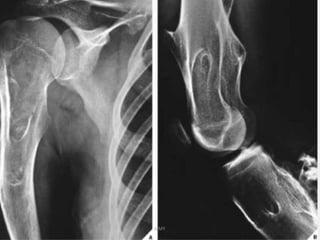

Hereditary multiple exostosis

- autosomal dominant

- 2 Genes-EXT1-Ch8 , EXT2- Ch 11

-< 10 yrs

Clinical features :

- knobby appearance

- short stature or even dwarf ( limbs short in relation to

trunk )

- Deformity of forearm - in 40 – 60 %

ulna short , radius bowed , loss of pronation n

supination ,

tibiofibular synostosis , genu valgum , coxa valga

Hereditary multiple exostosis UMY -autosomal dominant - 2 Genes-EXT1-Ch8 , EXT2- Ch 11 -< 10 yrs Clinical features : - knobby appearance - short stature or even dwarf ( limbs short in relation to trunk ) - Deformity of forearm - in 40 – 60 % ulna short , radius bowed , loss of pronation n supination , tibiofibular synostosis , genu valgum , coxa valga

• 30.

DD : multipleenchondromatosis , achondroplasia UMY Treatment : excision of symptomatic exostosis correction of deformity & limb length discrepancy